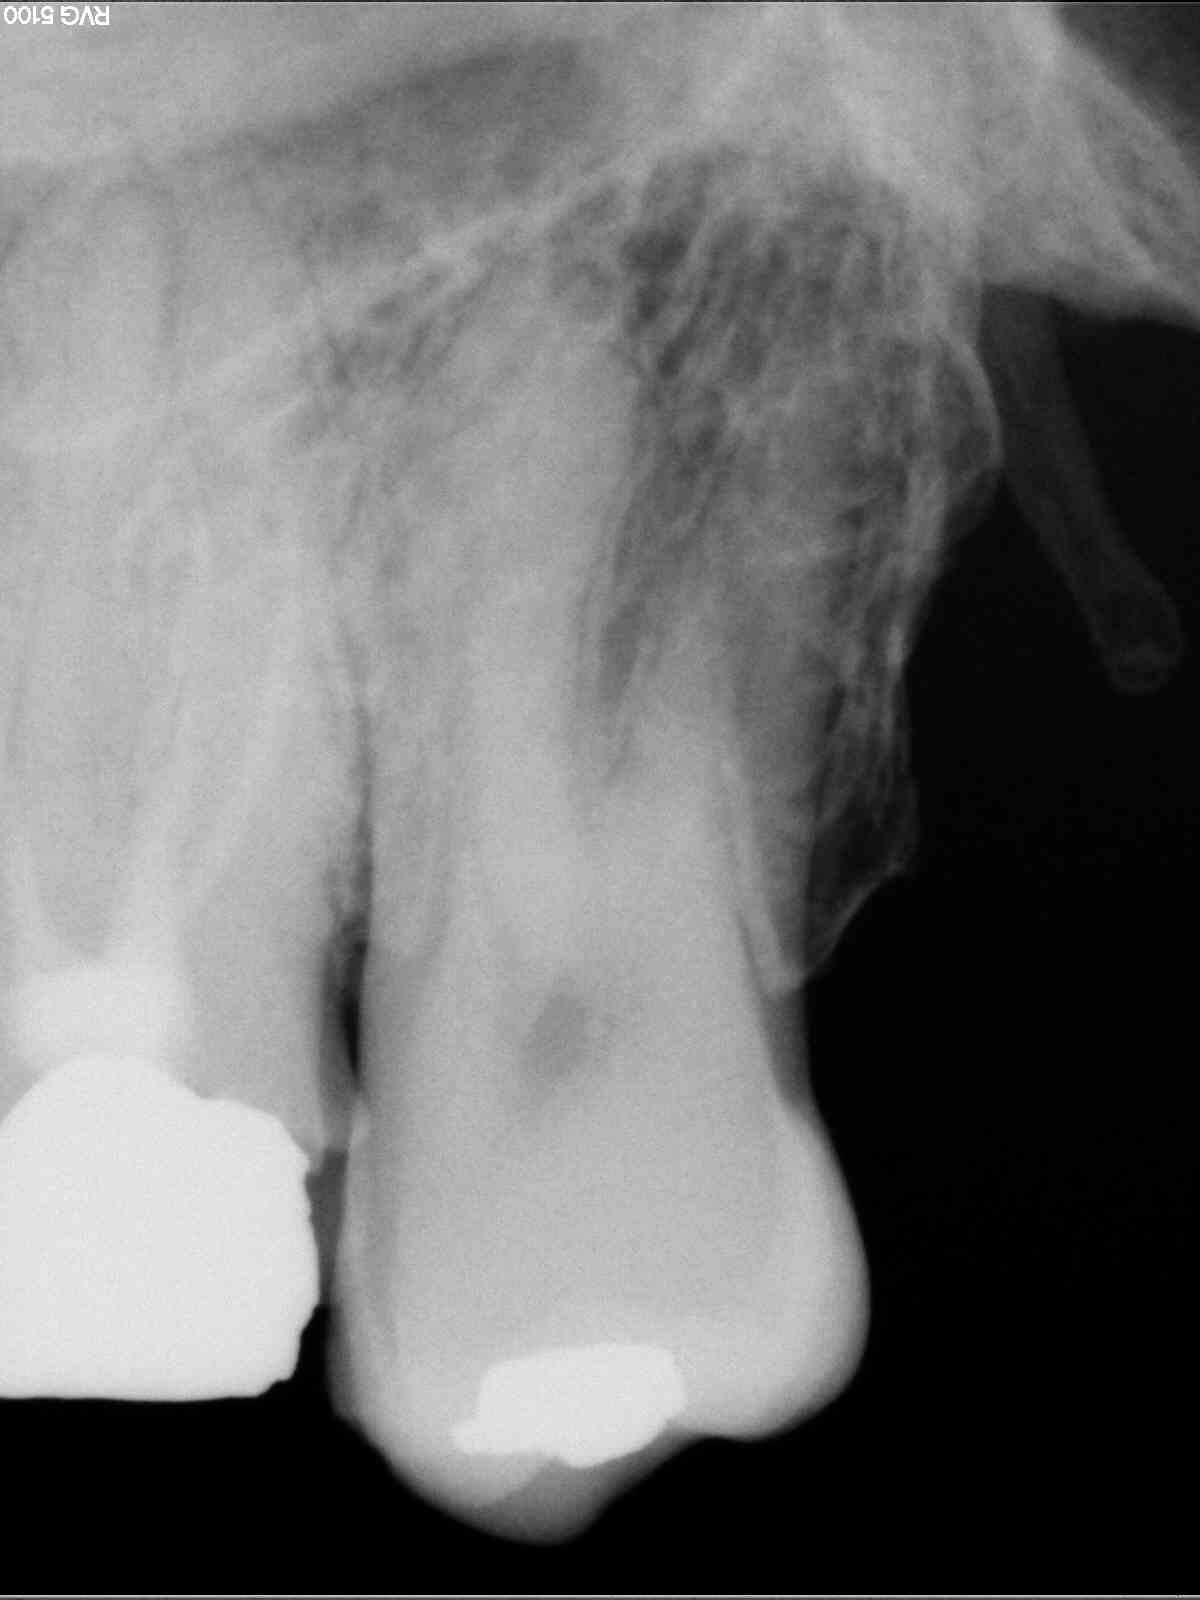

Radios1 dxb8my - Eugenol

Radios2 kprrcu - Eugenol

Radios3 auio0x - Eugenol

Radios4 pfsefa - Eugenol

Radios5 uwurgt - Eugenol

Radios6 ycayfo - Eugenol

Des inlay core... Des endos moisies... C est un français.

maladie dentaire diffuse + antécédent de choc (11 racine fracturée)